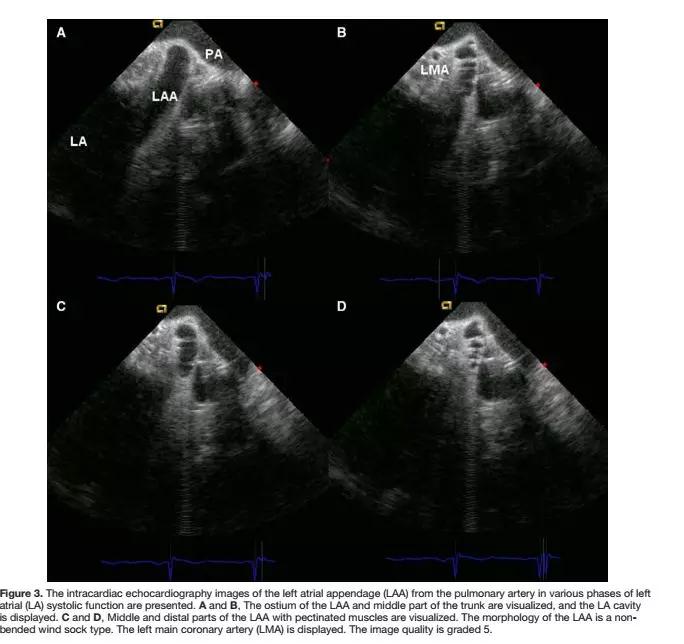

图注:ICE导管在肺动脉中观察到的左心房和左心耳的结构特征。A和B分别代表左心房收缩的不同时相。左心耳的口部、中间部分,以及整个腔体清晰可见。在左心耳中远端可观察到梳状肌(图C和D)。LMA代表冠脉左主干